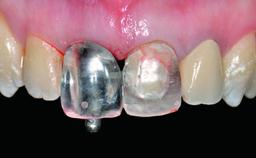

Replacement of a Compromised Upper Right Central Incisor: Hard- and Soft-tissue Augmentation, Late Placement of an RC Bone Level Implant

A 36-year-old male patient with a compromised maxillary central incisor was referred by his general dentist for consultation. The patient’s chief complaints were the gradual debonding of a temporary crown on the right central incisor and unsatisfactory esthetics due to an increasing diastema between the right central and lateral incisors. The patient reported a traumatic event some years previously, when a crown had been placed after root-canal treatment. The referring dentist wanted to provide a new crown restoration, but was concerned about the condition of the residual root. Anamnesis was negative for any other dental or periodontal pathology in the remaining dentition. The patient reported taking no medications: He was a smoker (10 to 15 cigs/day) and had realistic esthetic expectations.

Abutment Type CAD/CAM

Prosthesis Type FDP

Provisional Implant-Supported Prosthesis Prosthodontic margin > 3 mm apical to mucosal margin Prosthodontic margin > 3 mm apical to mucosal margin